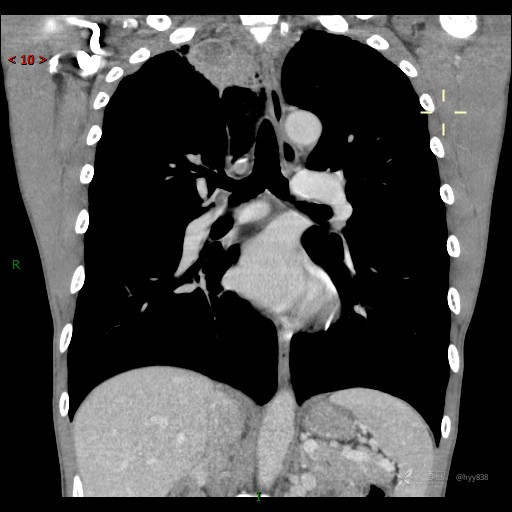

简要病史:患者自述8天前开始出现寒颤、发热,最高达39℃,自行口服退热药物治疗,每天两次,偶有咳嗽,无明显咳痰,无咯血,无头晕、头痛等不适,诉夜间出汗较多,无乏力、食欲减退等不适,为求进一步治疗于2023.4.2来我院门诊查胸部CT提示右肺尖占位,纵膈淋巴结增大,血常规白细胞升高,为求进一步治疗来院,门诊以“肺占位”收入我科。 患者自起病来,精神、饮食、睡眠可、大小便正常,体重及体力无明显改变。

辅助检查:CT

讨论:病变性质?